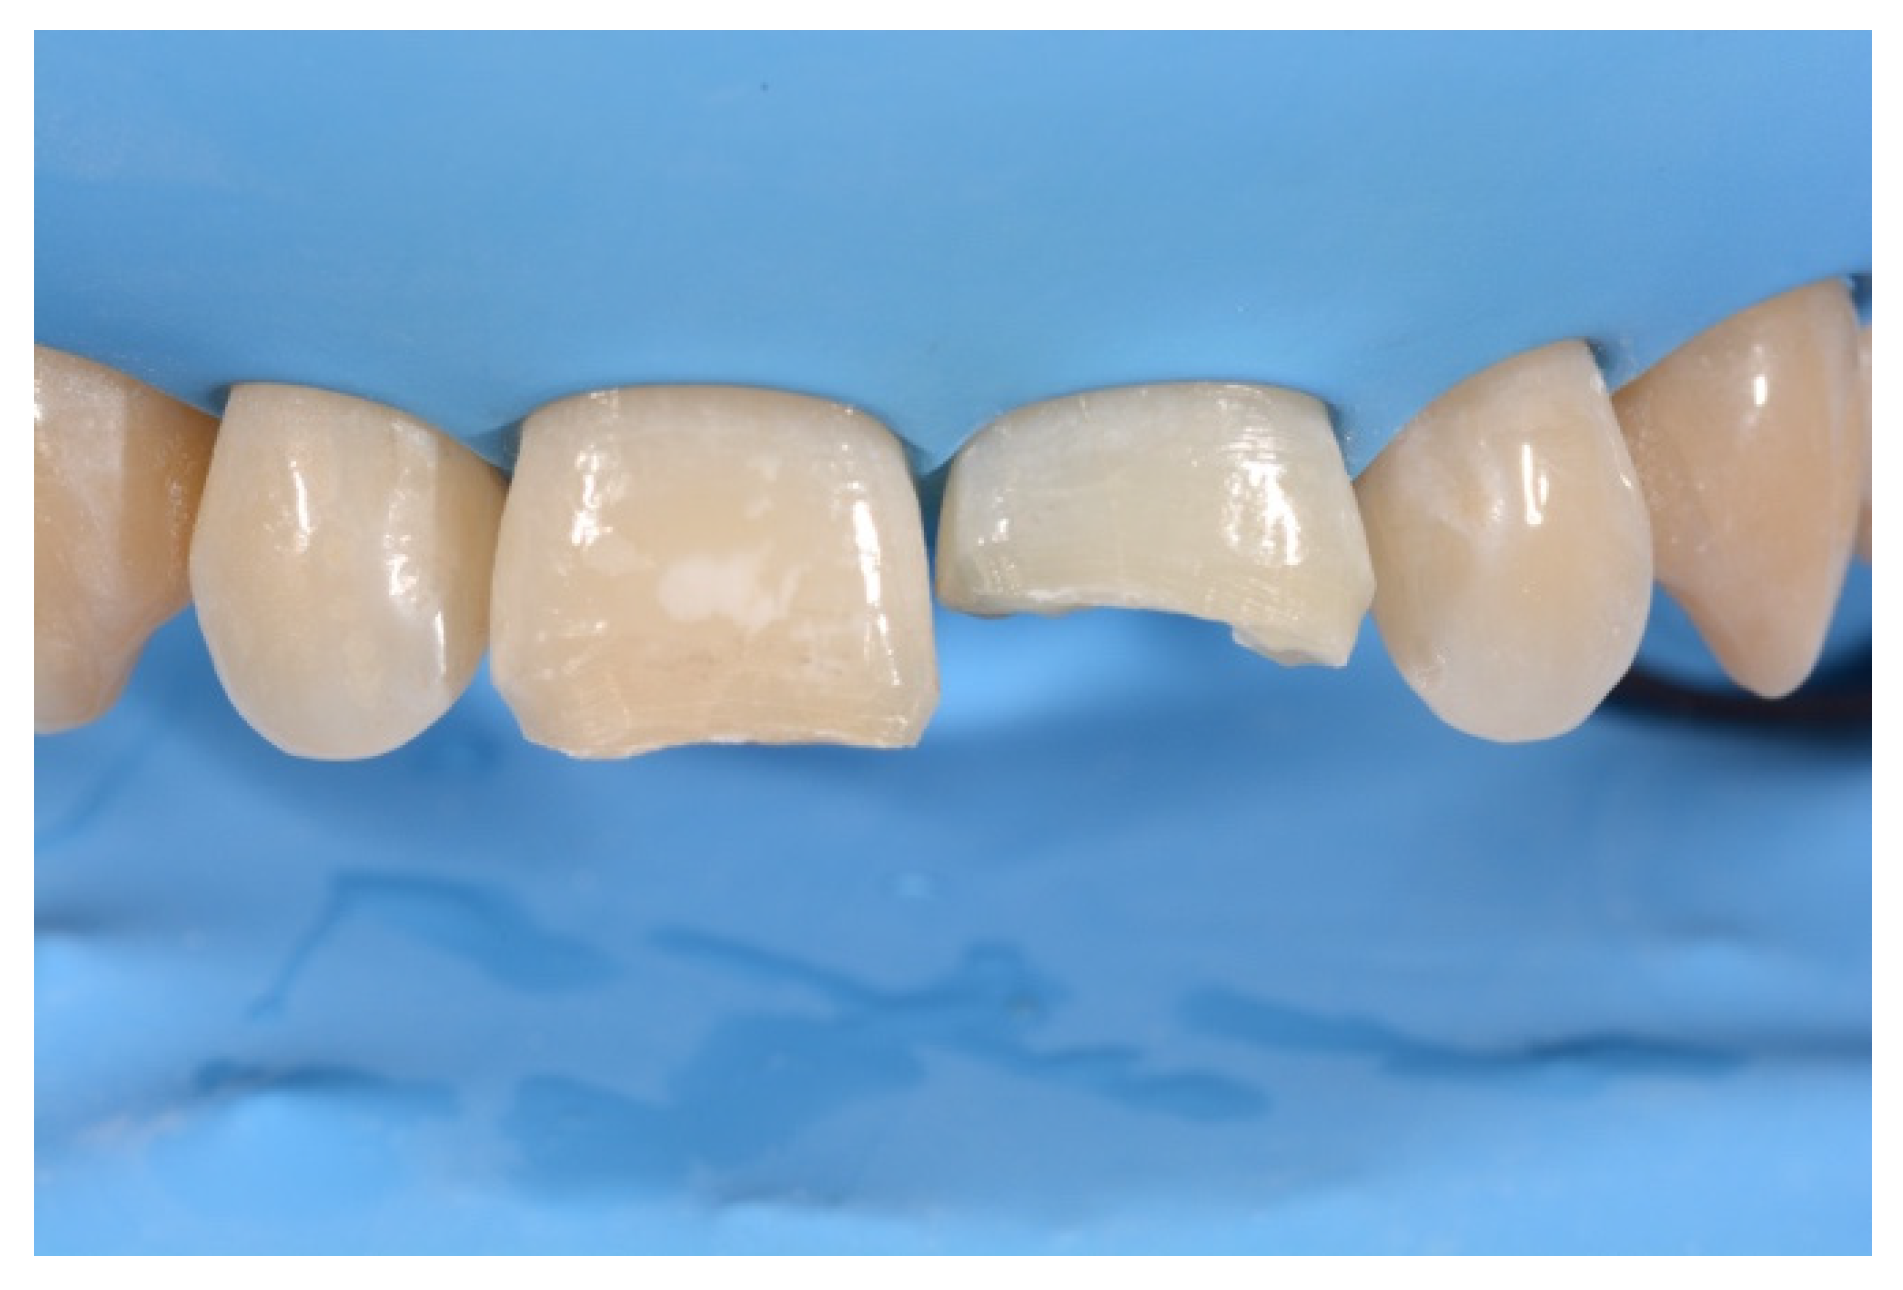

2. Case Presentation

- Building interproximal walls with matrices;